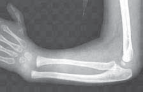

Chapter 51 Radial Dysplasia Reconstruction Scott N. Oishi and Marybeth Ezaki DEFINITION Radial dysplasia repr…